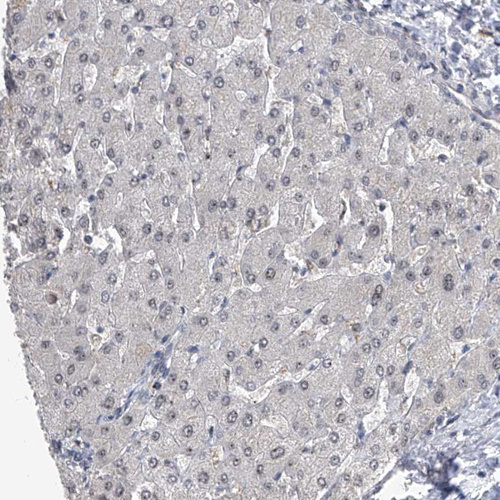

Immunohistochemistry analysis in human testis and liver tissues using HPA029979 antibody. Corresponding CMTR1 RNA-seq data are presented for the same tissues.